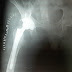

X-ray Abdomen Errect posture: Irregular radioopaque shadow are seen superimposed upon upper and mid part of the spine.